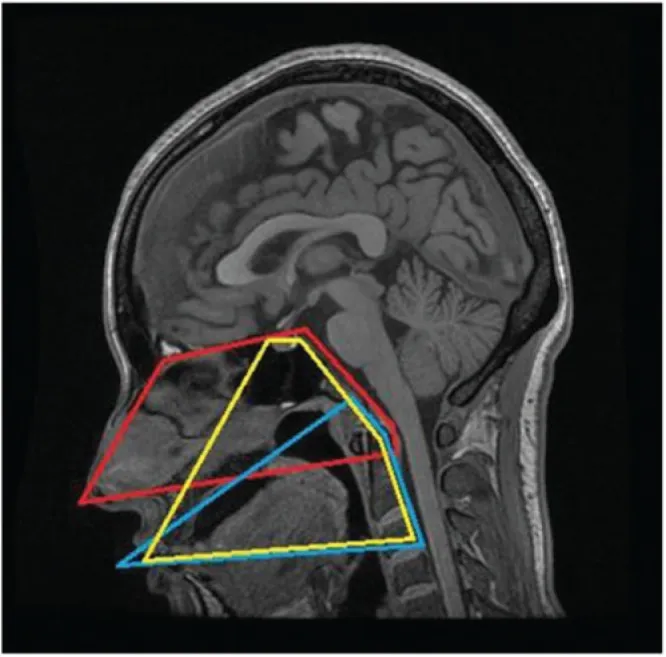

图示:在MRI的矢状中位面上每种方法的局限性。红线表示EEA,蓝线表示TOA,黄线表示TO-TPA。TO-TPA的手术视野在上部区域与EEA的手术视野重叠,在下部区域与TOA的手术视野重叠。

其上界可达前颅底,并能够显露至视交叉区域;其下界可抵达第三颈椎(C3)椎体水平。这使得该入路特别适用于处理从斜坡延伸至上颈段的病变。

内镜经鼻入路(EEA)

其上界同样可达前颅底,具体为额窦后壁;但其下界受硬腭的阻挡,通常限于第一颈椎(C1)水平。因此,对于向颅颈交界(CVJ)以下延伸的肿瘤,EEA的视野和操作会受到明显限制。